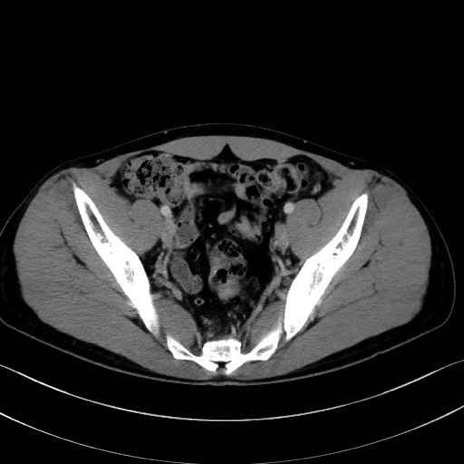

縫工筋 (Sartorius)